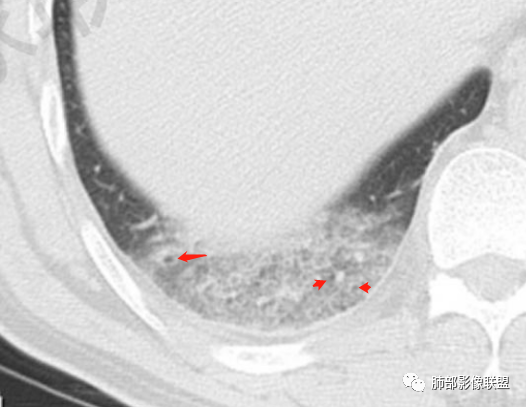

然后就是右下叶病灶的问题

后基底段,胸膜下,这个没问题吧

我们看看病变的形态、密度、边缘、内部改变

GGO密度

边缘不清

可惜没有重建,楔形?

细网格明显

支气管通畅,壁增厚

血管增粗

南边:首先应该不是气道来源的病变,气道的应该是小气道病变为主。

急性肺栓塞发生后,因肺动脉血流阻断而引起供血动脉远端肺组织的坏死称为肺梗死。肺动脉分支一旦血流阻断,远端毛细血管网则因管壁缺氧而通透性增高,液体及红细胞随之渗出,肺泡腔内渗出物增加,必然会影响气体交换,随后肺梗死发生。既往有研究表明,肺外周楔形阴影可以认为是肺梗死的征象,是唯一与肺栓塞显著相关的肺实性异常,该征象在肺栓塞患者中的发生率为25%。